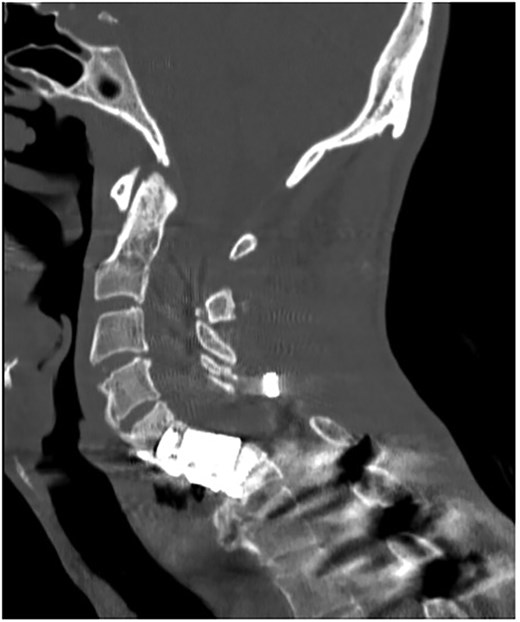

A 35-year-old male presented with a month-long history of dysphagia, severe headache, and posterior neck pain that radiated to the occiput. His medical history was significant for cervical surgeries, including an anterior cervical discectomy and fusion (ACDF) at C5/C6 one year and two months ago (Fig. 1). Shortly thereafter, the patient underwent revision surgery along with posterior plating from C5 to T1 due to osteomyelitis, worsening cervical deformity, and retropharyngeal abscess (Fig. 2). Initial workup included a noncontract computed tomography (CT), demonstrating increased gas density at C6 corpectomy site and post cricoid region (Fig. 3). A swallow study was obtained based on suspicion of a perforation and demonstrated extraluminal leakage of contrast posteriorly at the C6 level, consistent with initial CT (Fig. 4). Surgery included removal of the anterior and posterior hardware and esophageal repair. Although initially the esophageal injury was suspected to be related to the hardware, intraoperatively, it was found the instrumentation was not in communication with the esophagus. This confirmed the perforation was unrelated to direct injury from the cervical hardware construct, which was intact. The esophagus was repaired with a pectoralis flap. The postoperative course was uneventful, and the patient was discharged home after one week. The patient later died due to severe complications of substance abuse unrelated to the operation.

Sagittal CT of initial ACDF at cervical spine C5/C6 level over one year prior to esophageal perforation.